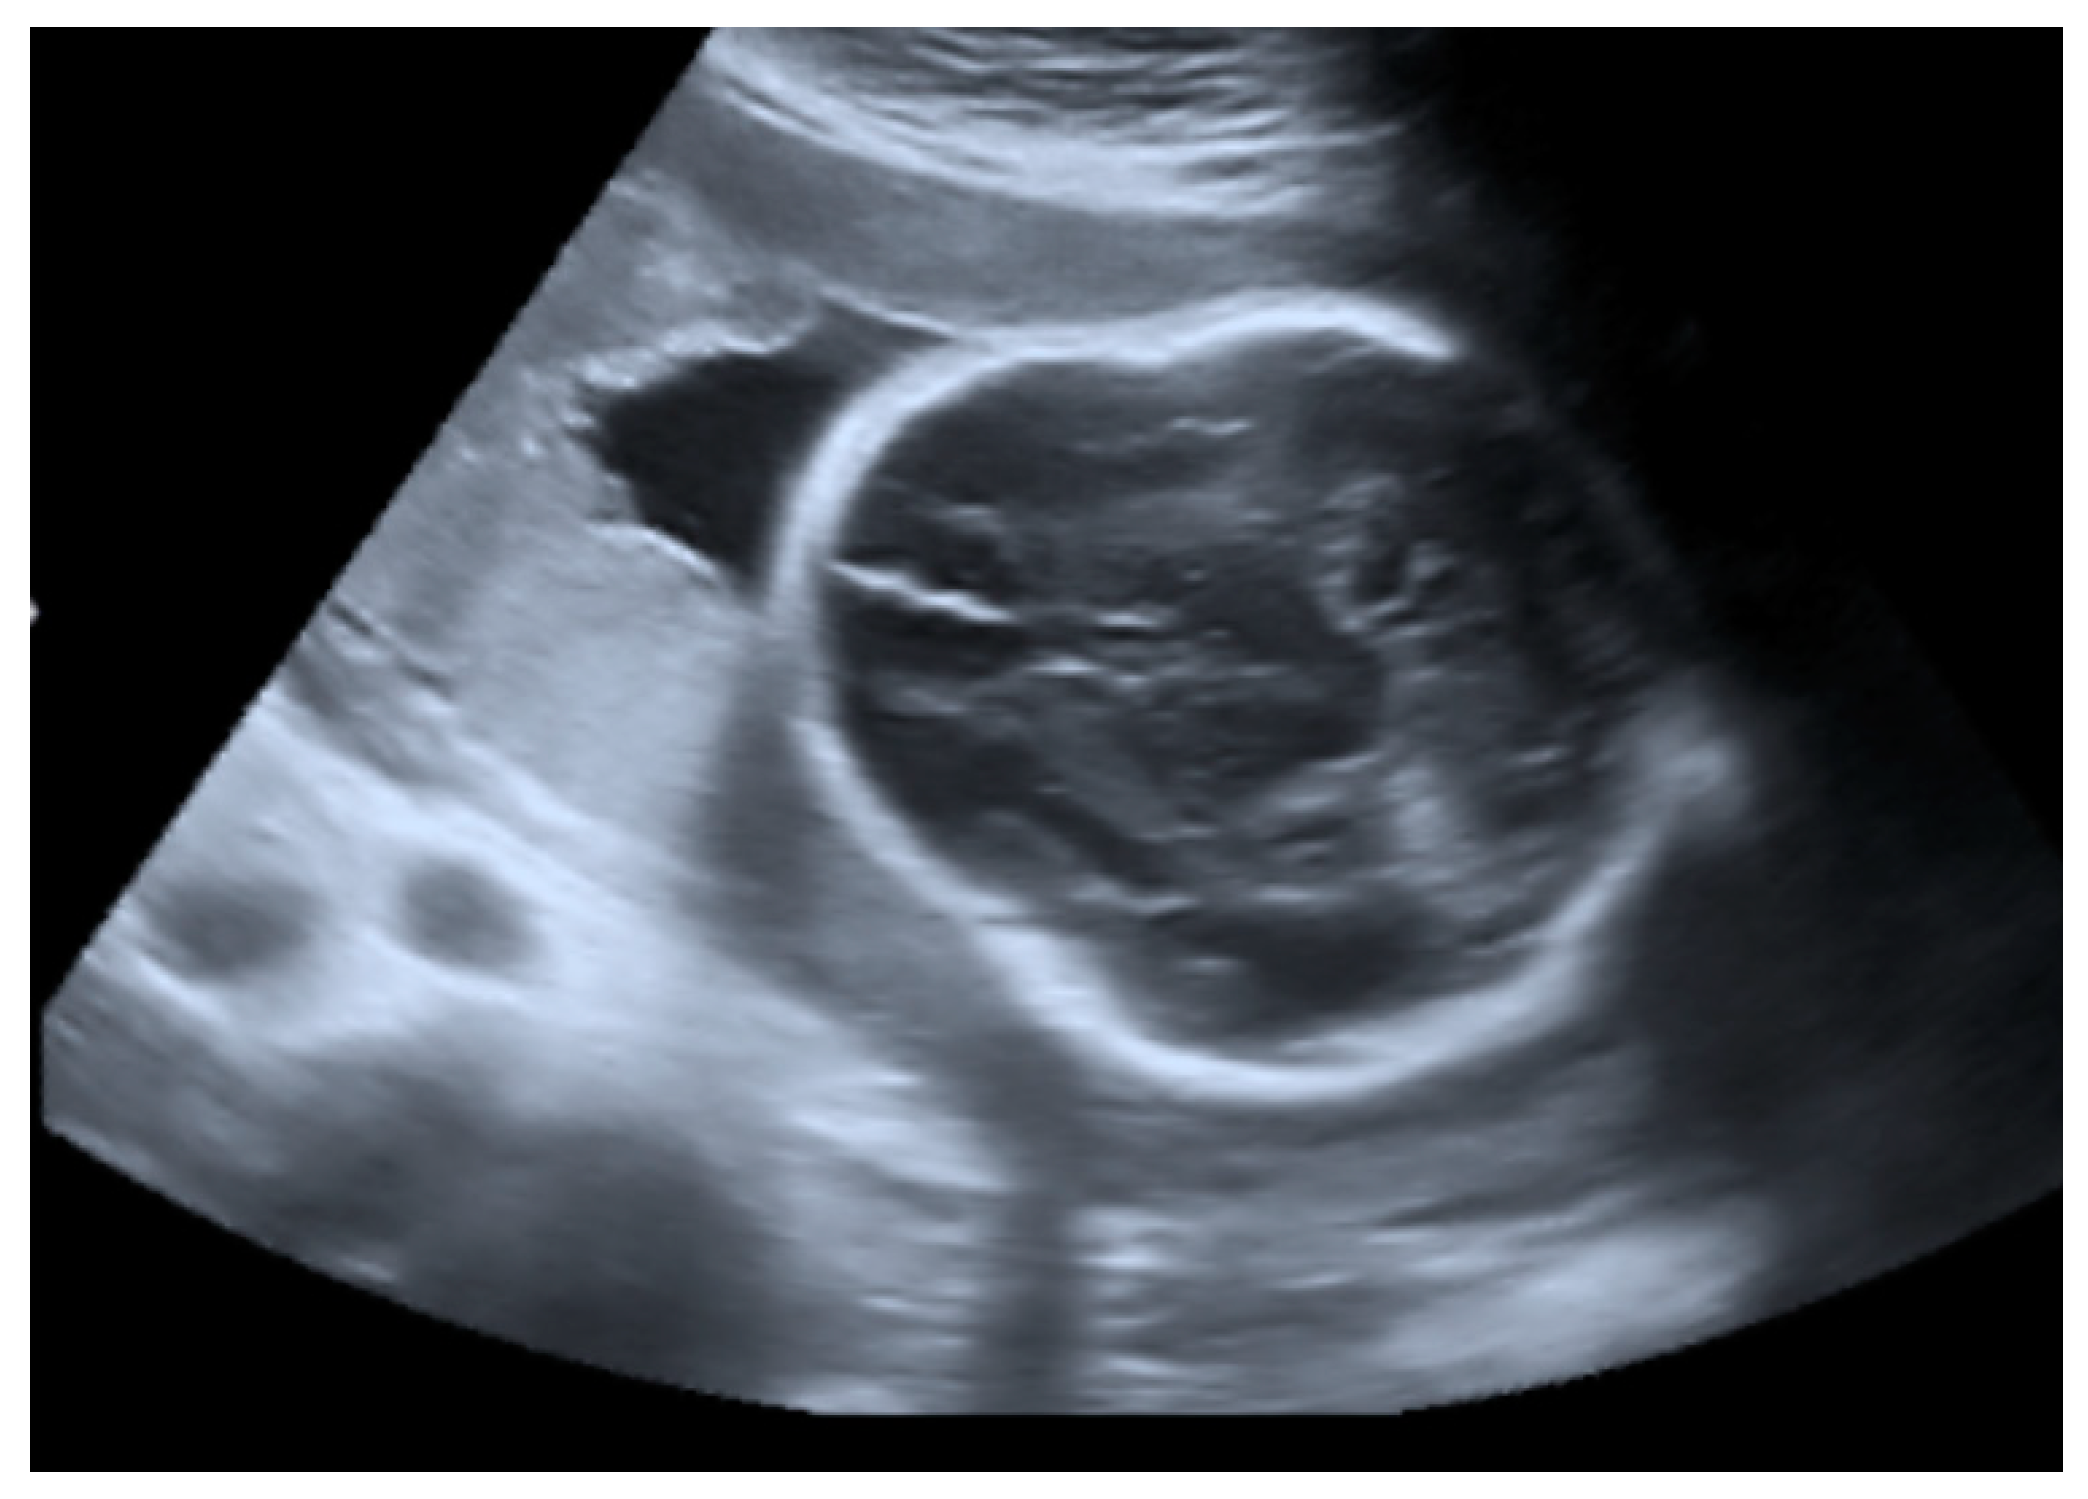

2.1. Prenatal Findings and Further Pregnancy Care